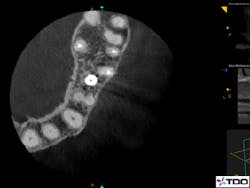

It is crucial to understand that a true endodontic failure can always be attributed to the presence of bacteria in the canal system or in the peririadicular tissues. The practitioner should determine the likely source of bacteria. Bacterial removal and elimination of infection are the ultimate goals of a successful retreatment. (2) This is done through proper diagnostic testing, radiographic assessment, and clinical judgment. Figure 1 shows an axial CBCT image of an untreated MB2 canal in the maxillary first molar.